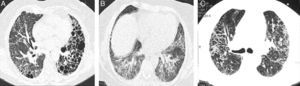

We had the initial HRCT of 33 patients, of these, 4 (12%) had a usual interstitial pneumonia (UIP) pattern, 12 (38%) had nonspecific interstitial pneumonia (NSIP) pattern and 17 (50%) had an indeterminate pattern with diffuse ground glass and reticulation images (Figs. 1 and 2). The median of the Kazerooni fibrosis scales was 0.47 and the median of the Kazerooni ground glass scale score was 2.33 (Table 3). We compared the response in the FVC at 6 months of follow up between patients with a value <0.47 of the fibrosis Kazerooni scale and those who had higher values. Those with lower Kazerooni scores (<0.47) were the ones who had a significant improvement in the FVC values (Table 4).

Basal CT images of a patient with ILD related to RA. (A) Multiple cystic images with perivascular and random distribution characteristic of lymphocityc interstitial pneumonia, and diffuse ground glass opacities and patchy areas of lung consolidations with broncocentric interstitium thickening. (B) One year follow up CT images after treatment with prednisone and methotrexate, showing less ground glass opacities, resolution of the consolidation areas and broncocentric interstitium thickening.